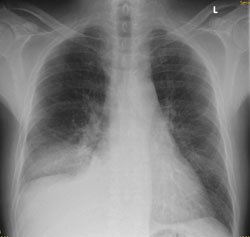

Ein 68-jähriger Patient mit chronischer Niereninsuffizienz und hypertensiver Herzerkrankung klagt akutell über zunehmende Dyspnoe. Sie veranlassen ein Thoraxröntgen.

Thorax pa

Thorax seitlich

Welcher Befund liegt vor? (mehrere richtige Antworten möglich)